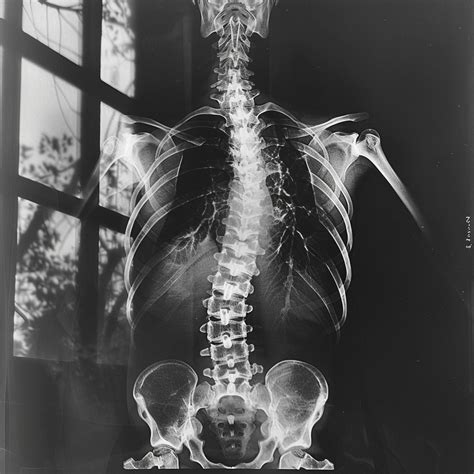

• Fractures

Each of these injuries has unique characteristics and requires specific care protocols. For instance, sprains involve the stretching or tearing of ligaments, while strains affect muscles or tendons. Fractures, on the other hand, involve broken bones and often require immobilization and surgical intervention.